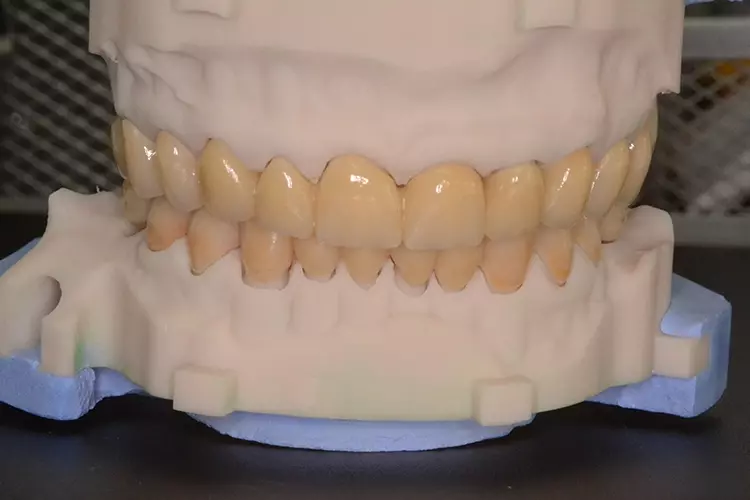

Neugestaltung der Front bei starken Zahnfehlstellungen

Bei dem heute 49-jährigen Patienten wurde seit Kindertagen versäumt, die Ober- und Unterkieferzahnbögen kieferorthopädisch auszurichten. Der Patient leidet seitdem stark unter seinen Zahnfehlstellungen.

Die Fraktur des stark elongierten Zahnes 21 war für den Patienten der Ausgangspunkt, sowohl die Front des Ober- als auch des Unterkiefers prothetisch überarbeiten zu lassen. Dabei wurde der frakturierte Zahn 21 durch ein navigiert eingesetztes Sofortimplantat ersetzt, während die verschachtelt stehenden Zähne 12 und 42 durch eine Brückenversorgung korrigiert wurden (Abb. 4a-j).